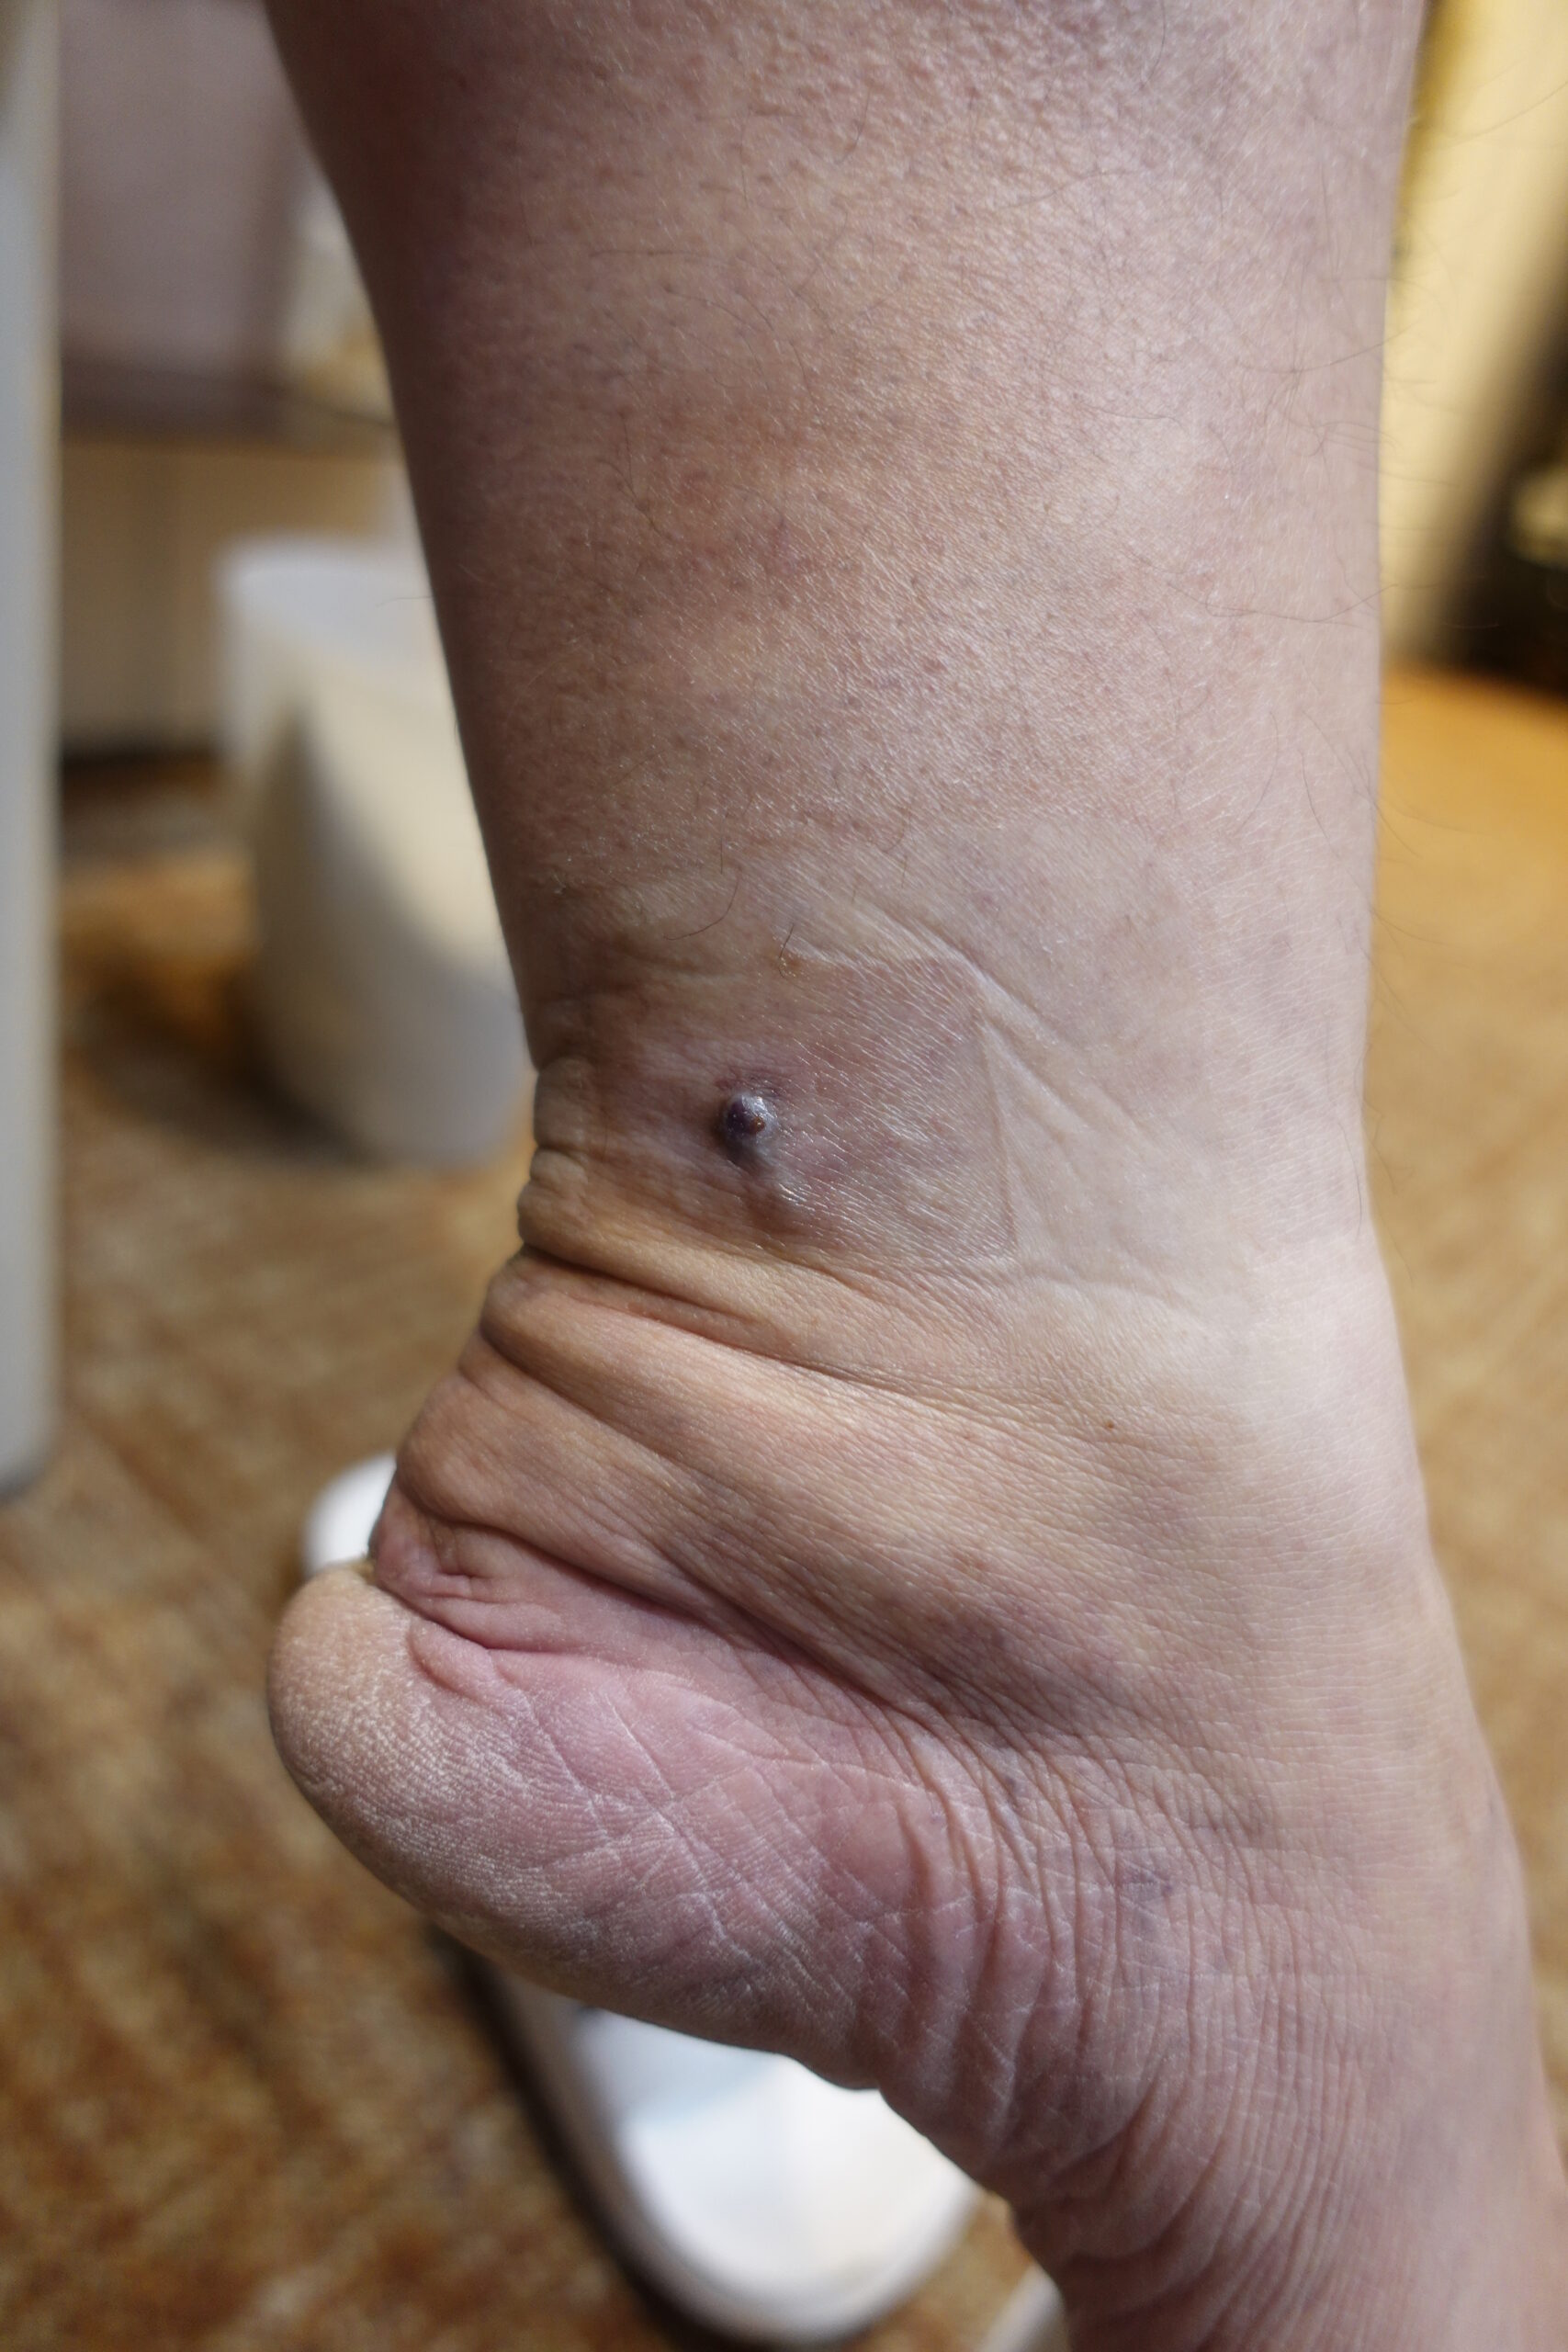

溢血点・溢血斑 - 法医学ブログ。

皮下溢血の程度は骨損傷の程度に比例するか? : 整骨太郎のひとりごと。

皮膚の点状出血が起こるのはなんで?考えられる原因や疾患を解説。

2025年版 内出血と皮下出血の原因から治癒過程まで徹底解説!血液データ・脳卒中後の薬剤との関連性と観察ポイントも詳述 – STROKE LAB東京 大阪 自費リハビリ脳卒中 神経系。